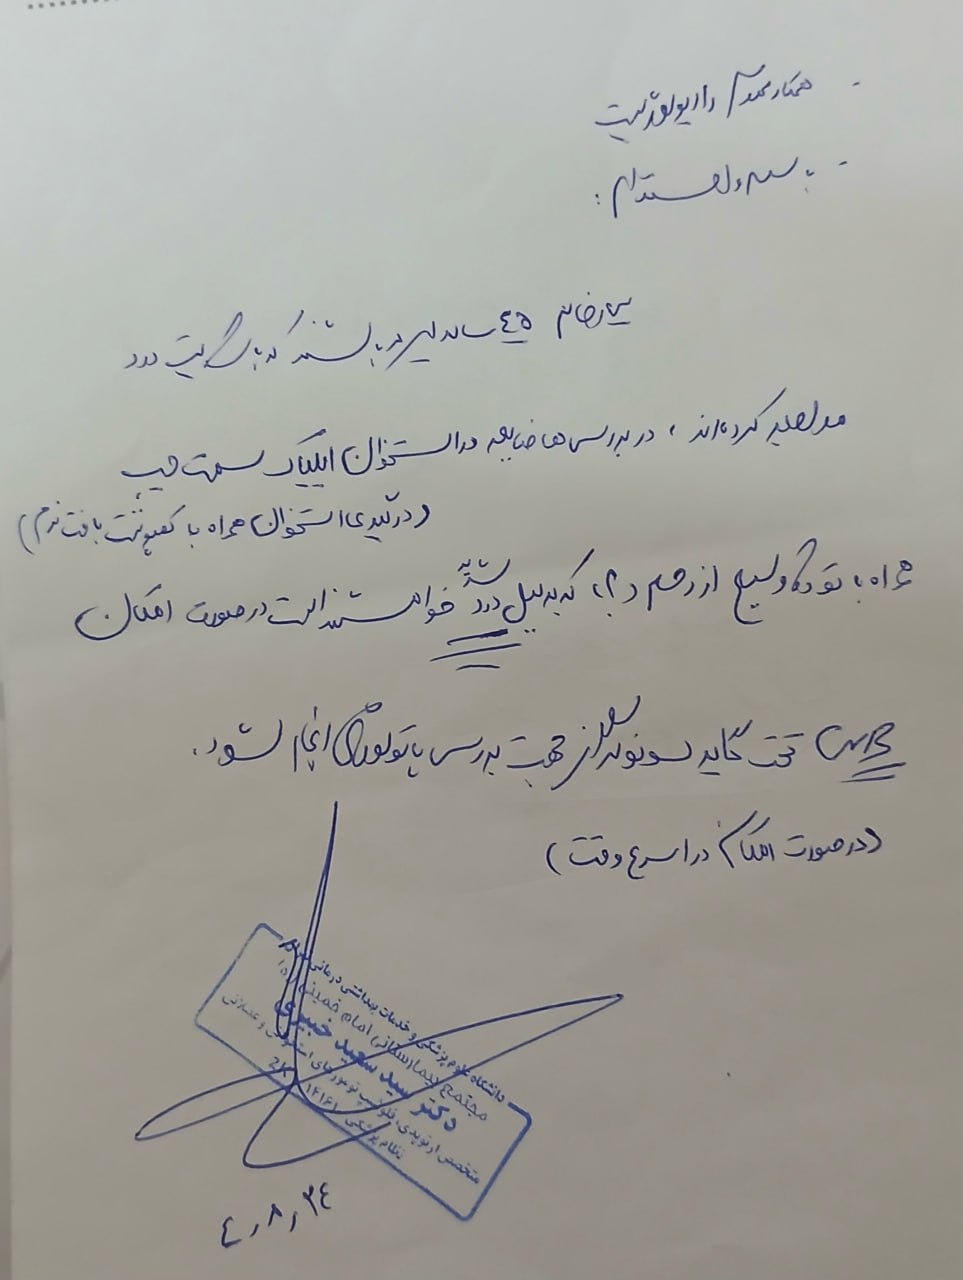

در بررسیهای تصویربرداری (MRI)،در تاریخ 24.7 ، تودهای با تشخیص کندروسارکوما همراه با DVT گزارش شده است. بیمار سابقه درد لگن داشته که شدت آن در حال حاضر نسبت به گذشته کاهش یافته است. به گفته بیمار، حجم توده در ابتدا در حدود اندازه یک تخممرغ بوده که در حال حاضر کاهش یافته است. همچنین تورم اندام تحتانی در حال حاضر نسبت به قبل کمتر شده است.

مراجعه کرده است. پس از بررسی های انجام شده در MRI انجام شده توده با درگیری مفصل ساکروایلیاک چپ و DVT؛ ابتدا تحت درمان DVT قرار گرفته است و سپس جهت پیگیری تومور رویت شده تحت بیوپسی قرار گرفته است و با تشخیص کندروسارکوما به این مرکز مراجعه کرده است و تحت کموتراپی و رادیوتراپی قرار گرفته و سایز تومور کاهش یافته است.